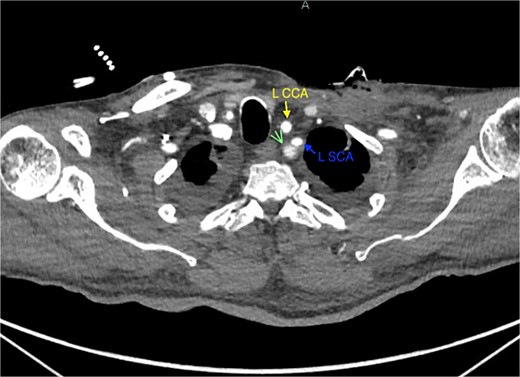

A 67-year-old male with a medical history significant for hypertension, diabetes, coronary artery disease, carotid artery stenosis, osteoarthritis, and 50 pack-year smoking history presented initially to an orthopedic surgery office for evaluation of left shoulder pain after exercising. The patient was found to have an underlying rotator cuff injury and was subsequently treated with cortisone injection. The patient subsequently developed septic arthritis, ultimately requiring incision and drainage of the abscess and resection of the sternoclavicular joint, partial first rib, and partial clavicle. The patient required multiple washouts and debridement procedures, ultimately leading to septic shock and bacteremia requiring close observation in the surgical intensive care unit. A computed tomography angiogram (CTA) of chest was performed at the time and revealed a subcentimeter penetrating ulcer, arising from the proximal left subclavian artery likely secondary to surgical trauma, which was observed nonoperatively given the patient critical status in the intensive care unit (ICU) (Figs 1 and 2). During the ICU course, the patient developed left upper extremity swelling A left upper extremity duplex ultrasound subsequently revealed a nonocclusive deep vein thrombosis of the subclavian vein and also showed resolution of a pseudoaneurysm (PSA) of the subclavian artery. The patient was started on anticoagulation at this time for a deep vein thrombosis (DVT). The patient was ultimately discharged upon resolution of his acute infection to a rehabilitation facility. During the third-month follow-up office visit, the fistulous connection between the subclavian artery and vein was found incidentally on left upper extremity duplex ultrasound (Fig. 3). Physical exam of the patient was otherwise unremarkable with palpable upper extremity pulses and the patient did not appear to have any symptoms related to the fistula including upper extremity swelling or open wounds. The patient was scheduled for an elective repair of the fistula via endovascular stent graft placement. The patient was brought to the operating room, and the radial artery was accessed with a micropuncture device. Radial artery access was our choice to intervene given the location of fistula. When left upper extremity angiography was performed, it revealed a blush of contrast from proximal subclavian artery, revealing a small fistula between subclavian artery and subclavian vein (Fig. 4). Subsequently, a 6 × 29 mm balloon-mounted stent graft was used to cover the fistula. Completion angiography was performed showing adequate seal with resolution of the fistula (Fig. 5). The patient tolerated the procedure well and was subsequently discharged from the hospital the same day. He was started on antiplatelet therapy post-operatively and continued oral anticoagulation for the DVT. The patient was seen in the office at 3-month follow-up, where a repeat duplex ultrasound revealed normal waveforms and velocities throughout the left arm. He was also seen in the office recently, and he is doing well with no new complaints.

Demonstration of pseudoaneurysm of the proximal left subclavian artery on axial image (green arrow: L SCA PSA, blue arrow: left subclavian artery, yellow arrow: left common carotid artery).

Demonstration of pseudoaneurysm of the proximal left subclavian artery on axial image (green arrow: L SCA PSA, blue arrow: left subclavian artery).